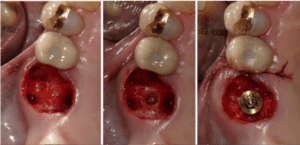

„Klinischer Stellenwert und Management der biologischen Breite am Implantat“